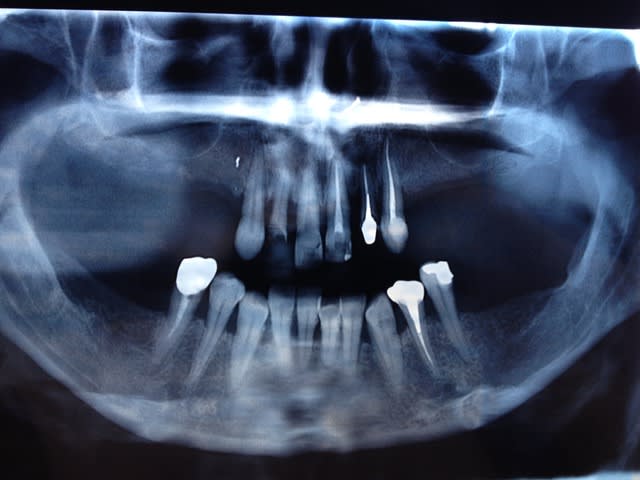

J'aimerais votre avis sur ce cas.

Il s'agit d'une patiente de 45 ans, célibataire, femme de ménage, très complexée par sa bouche mais coquette. Elle est phobique du dentiste avec anxiété et manque de confiance..

Elle est aujourd'hui arrivée à un point de "non-retour", elle ne peut plus repousser ou bricoler petit à petit comme ses 10-20 dernières années. Elle semble prête à une reconstruction globale.

Que proposez vous en prenant en compte son profil et sa situation financière (faible à modérée) ?

avec seulement la pano c'est chaud, ajoute quelques photos

Vu la perte d´insertion des dents du haut. Je partirais pour un complet du haut immédiat.

Pour le bas juste avec la pano je ne me mouille pas.

Il serait regrettable d’extraire le bloc antérieur du maxillaire et perdre tout le volume osseux. Sa situation financière peut évoluer. La conservation osseuse est aussi incontournable dans la dentisterie moderne que celle des dents.

Mon souci ici , c'est la paro du bloc supérieur.